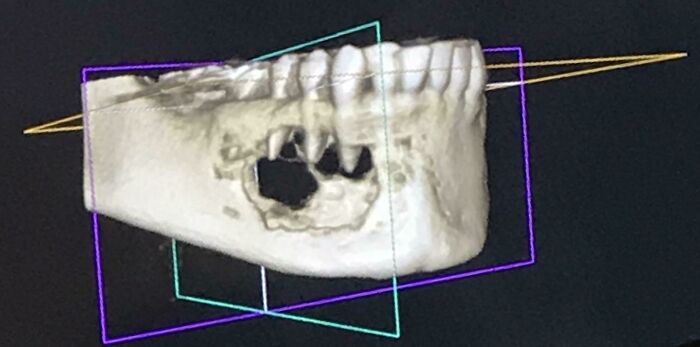

#9 Išiel som na čistenie zubov minulý mesiac a spomenul som pocit necitlivosti v zube – bol som šokovaný, keď sanašiel nádor, ktorý mi požieral čeľustnú kosť. Táto fotografia je môj CT sken